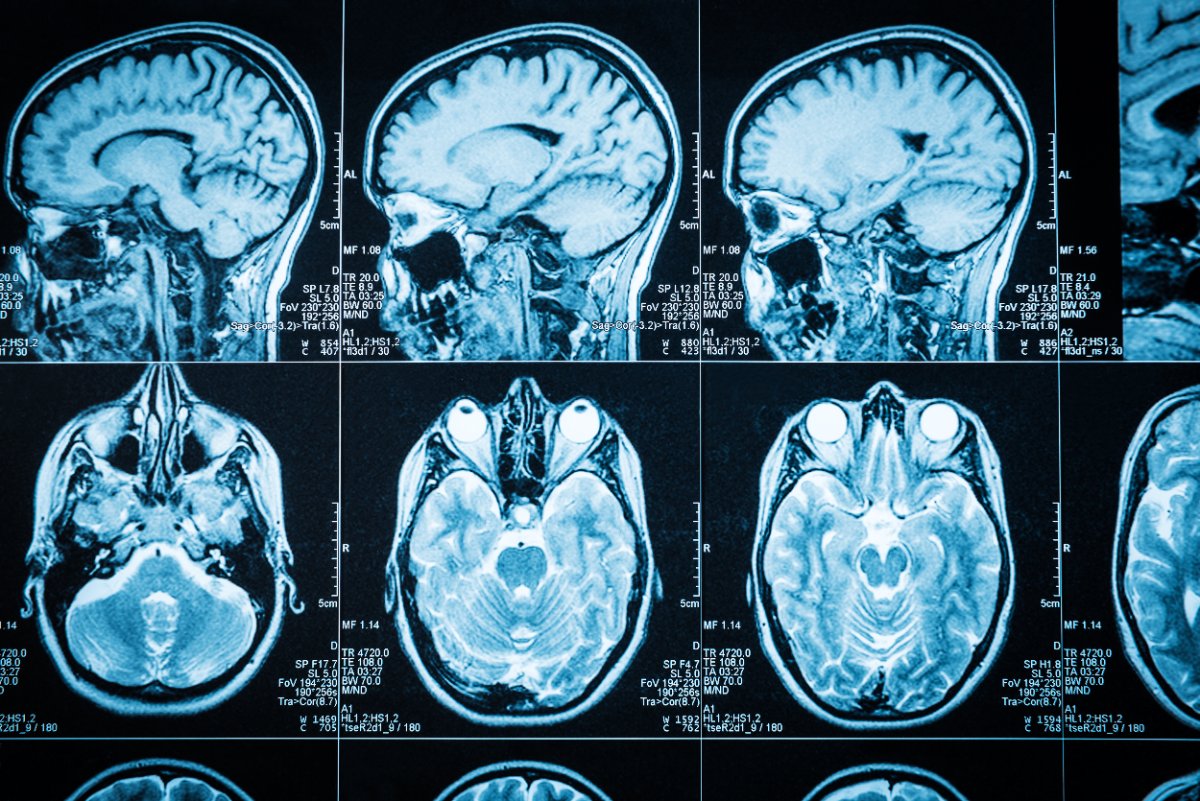

How CO exposure leads to brain injuries

Prolonged carbon monoxide exposure causes a buildup in the blood. The odorless, colorless, and tasteless gas binds to red blood cells, wreaking havoc on the body. When people are exposed to carbon monoxide for long periods, it can lead to lasting damage to the brain from a lack of blood flow and cellular damage.